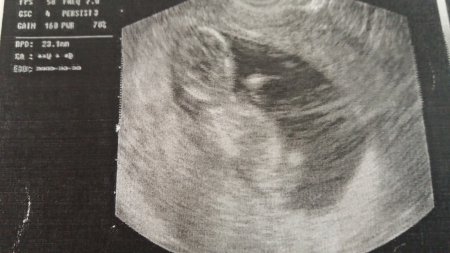

4. Jak vypadá miminko 12. týden těhotenství?

Plod měří na konci tohoto týdne od temene k zadečku asi 6cm, váží asi 10-13q.

Plod stáří 11+2 týdne a velikosti 47 mm. Je vidět hlava s nosem, jasnější horní a dolní čelistí. Vpravo pak dolní končetiny.